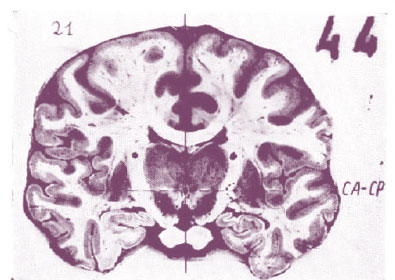

International Journal of Neurology Magazine / Brain Tumors

Brain Tumors